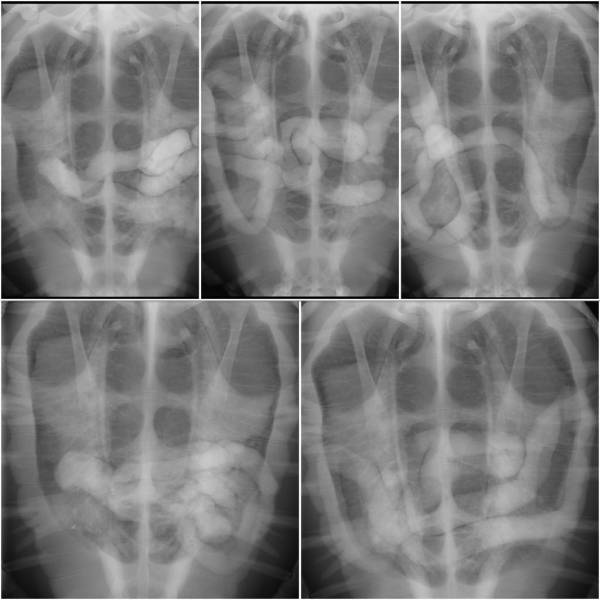

We grew quite concerned about this and X-rayed her to find out more. It turned out that Moya had impaction; her gut wasn’t working properly so nothing was moving. We thought this may have been caused by a blockage. An X-ray contrast study was started and she was taken for an MRI scan. No clear obstruction was revealed, and Moya started pooping soon after that - we thought she was out of the woods.

However, in late February, Moya again stopped pooping. After another MRI and contrast study, it was determined that she had air bubbles in her gut, this was due to a lack of peristalsis (the movement your intestines make to push things along). Even though she had started pooping after the previous scans, her intestines were still struggling to recover.